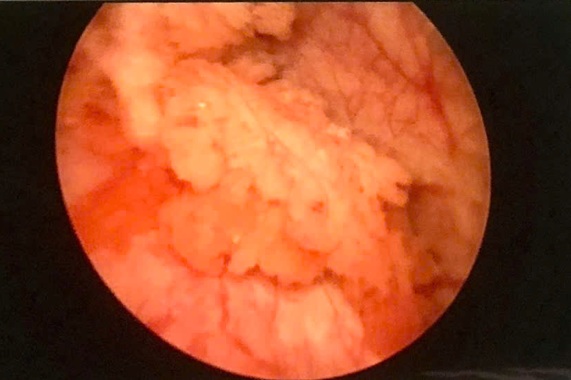

Vừa qua, Trung tâm Tiết niệu của Bệnh viện Trường Đại học Y Dược Cần Thơ vừa điều trị thành công hai trường hợp tiểu máu kéo dài, điều trị nội khoa không thuyên giảm. Hai trường hợp bệnh được siêu âm, nội soi bàng quang chẩn đoán và chụp cắt lớp vi tính hệ tiết niệu ghi nhận bướu bàng quang nông, bờ không đều, ngấm thuốc tương phản. Các bệnh nhân được chỉ định nội soi niệu đạo cắt đốt bướu bằng laser.

Hình ảnh bướu bàng quang ở thành bên phải bàng quang trước phẫu thuật